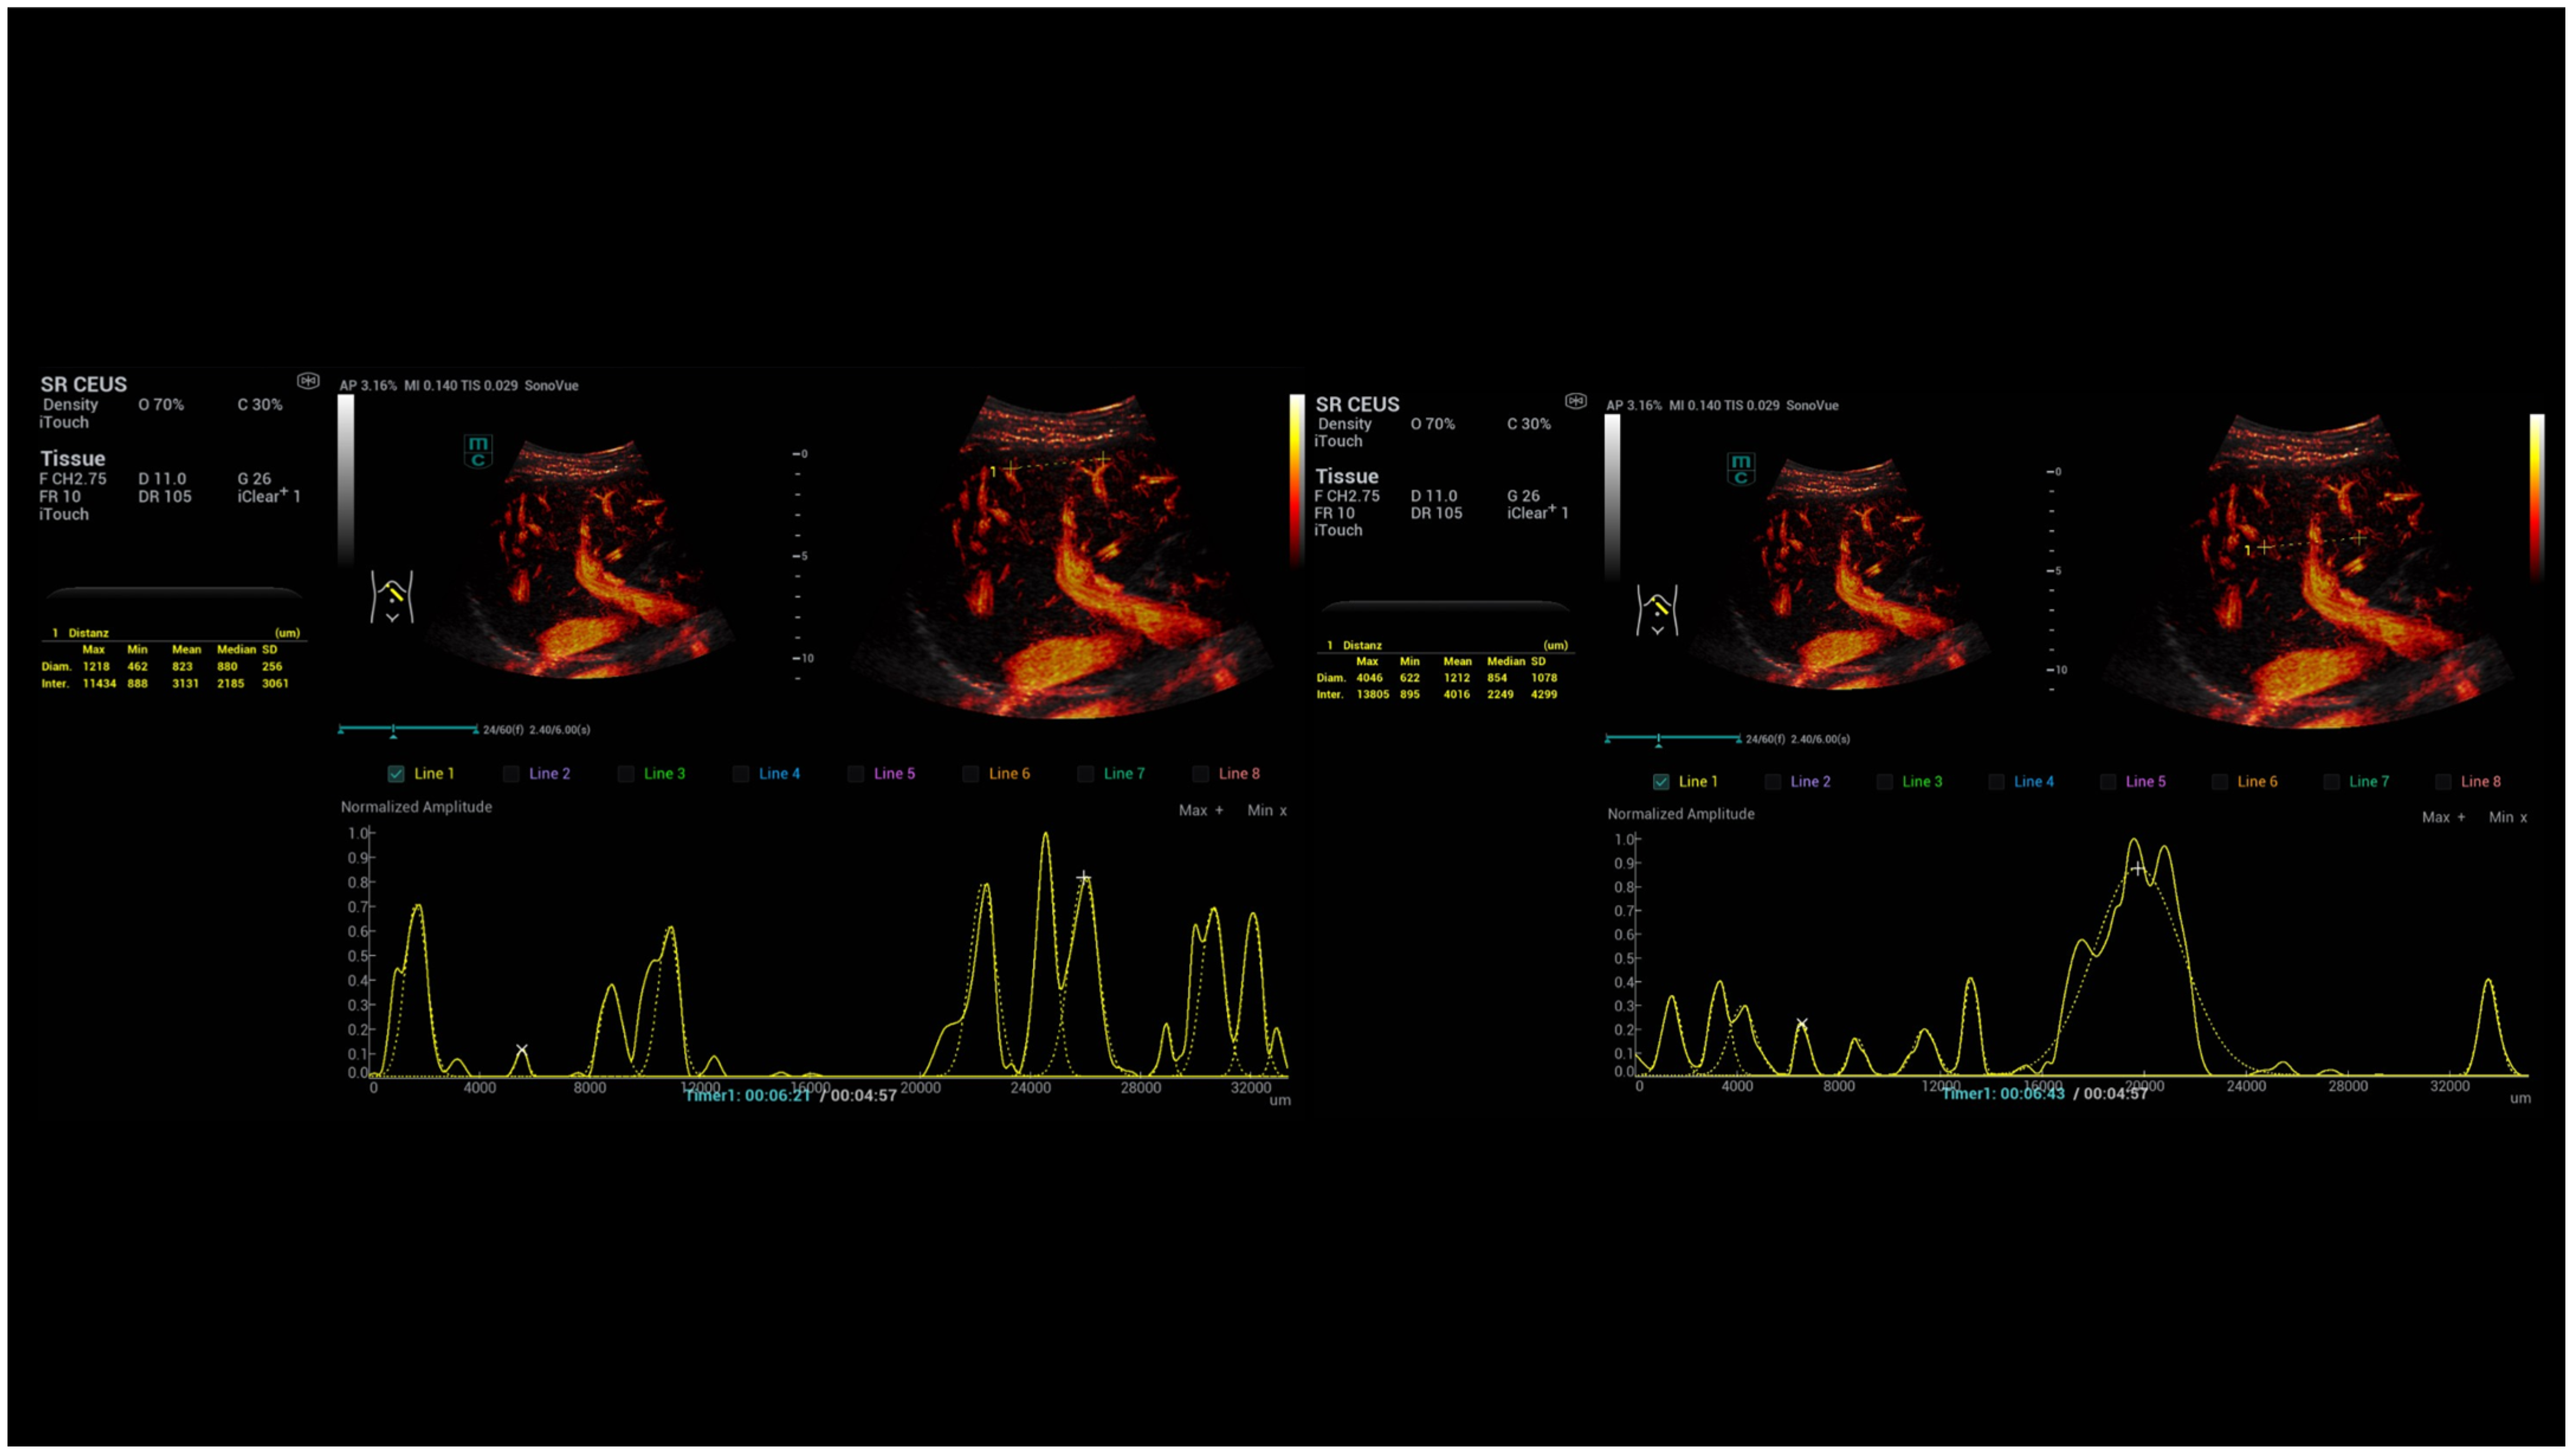

- Kaiser, U.; Vehling-Kaiser, U.; Kück, F.; Gilanschah, M.; Jung, F.; Jung, E.M. Super-Resolution contrast-enhanced ultrasound examination down to the microvasculature enables quantitative analysis of liver lesions: First Results. Life 2025, 15, 991. [Google Scholar] [CrossRef]